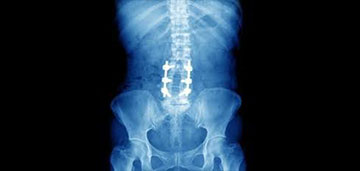

Spine Surgery

Spine Fusion